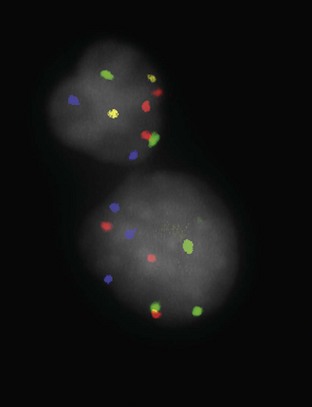

The second pathway leads to the development of high-grade cancer including CIS, T1, and, ultimately, muscle-invasive carcinoma. Such genetic alterations can be evaluated using karyotyping, microsatellite analysis for allelic imbalance (Mao et al, 1996), comparative genomic hybridization (Kallioniemi et al, 1995), DNA ploidy analysis by flow cytometry (Bittard et al, 1996), and fluorescence in-situ hybridization (FISH) (Degtyar et al, 2004). These evaluations can show that low-grade papillary tumors tend to exhibit relatively few chromosomal abnormalities, primarily involving loss of all or part of chromosome 9 (particularly the q arm). In contrast, high-grade tumors tend to have numerous and greatly variable chromosomal gains and losses. In addition to their relatively predictable aneuploidy, high-grade tumors can also lose all or part of chromosome 9 (Richter et al, 1997). Although almost any chromosome can be affected, aneuploidy of chromosomes 7, 9, and 17 is associated with especially aggressive tumors (Olumi et al, 1990; Waldman et al, 1991; Degtyar et al, 2004).

The necessity of biopsy to determine BCG response is unclear, although it should be strongly considered in high-risk patients to determine disease status at this key point in time. Urine cytology can be useful in this setting. Dalbagni and colleagues (1999) reported minimal utility in routine biopsy after BCG if cystoscopy and urinary cytology were both negative. Whereas 5 of 11 patients with erythematous bladder mucosa and positive cytology had positive bladder biopsies, none of 37 with erythematous lesions and negative cytology was positive, and only 1 in 13 patients with a normal mucosa had positive biopsies (Dalbagni et al, 1999). Other studies have suggested that the value of routine post-BCG biopsy is limited (Dalbagni et al, 1999). UroVysion FISH (Abbott Molecular, Chicago) conversion from positive to negative has been shown to correlate with BCG response in single-center studies (Kipp et al, 2005; Whitson et al, 2009).